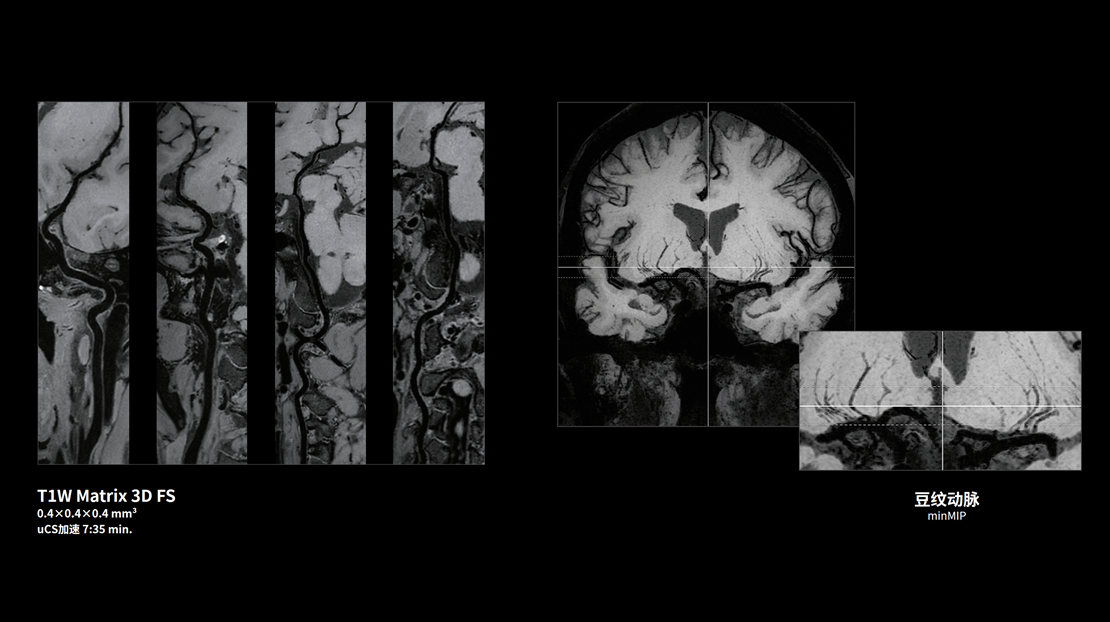

高分辨血管壁 T1W Matrix 3D FS

0.1mm超高分辨神经解剖成像